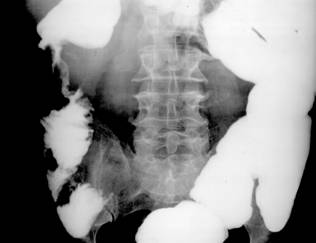

Fig. 49 – Diverticuli colici (magini aditionale opace, rotunde sau ovalare, net conturate, de dimensiuni variabile, sesile sau pediculate)

Sunt expansiuni circumscrise ale peretelui colic, in a caror structura intra toate straturile anatomice (in cazul diverticulilor congenitali) sau numai mucoasa herniata intr-o zona de slaba rezistenta a tunicii musculare (diverticulii dobanditi). In functie de mecanismul de producere pot fi:

- diverticuli de pulsiune – apar ca imagini aditionale opace, rotunde sau ovalare, net conturate, de dimensiuni variabile, sesile sau pediculate, ce se evacueaza uneori cu dificultate (diverticulita).

- diverticuli de tractiune – realizeaza opacitati aditionale de forma triunghiulara cu baza pe lumen, neregulat conturate.